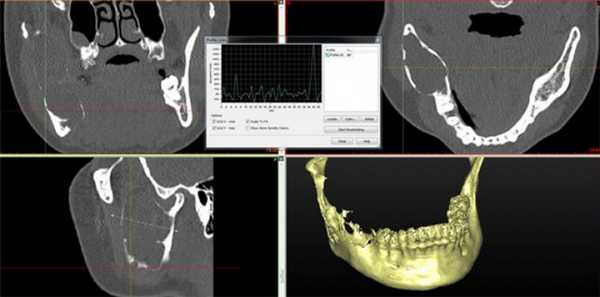

Пациент муж., 50 лет, в анамнезе операция удаления амелобластомы в пределах видимо здоровых тканей. Обратился с жалобами на повторное развитие опухолеподобного образования (Рис. 4).

Рис. 4. КТ свидетельствует о рецидиве кистозной формы амелобластомы.

Поражено тело нижней челюсти больше справа, определяется «вздутие» и неравномерное истончение передней пластины тела челюстной кости, обширный участок деструкции с четкими, полицикличными контурами, неправильной овальной формы, размерами 4,5 х 3,5 х 3,0 см. Кортикальный слой передней поверхности челюсти значительно истончен, местами не определяется, периостальная реакция отсутствует. В патологически измененном участке видны перегородки и известковые включения. Правое ментальное отверстие и дистальный отдел канала правого нижнеальвеолярного нерва не определяется.

Клинический случай №4

Пациент муж., 32 года (Рис. 5).

Рис. 5. КТ свидетельствует об объемном образовании нижней челюсти, требующем верификации.

Поражена правая ветвь нижней челюсти. Определяется объемное кистозное образование, овальной формы с четкими полицикличными контурами, замещающее весь венечный отросток и распространяющееся на суставной отросток. Объем кости увеличен за счет вздутия. Кортикальный слой значительно истончен, местами не прослеживается. Канал нижнеальвеолярного нерва вплотную прилежит к образованию, верхняя его стенка в проксимальном отделе не прослеживается. В подьязычной области справа виден лимфоузел, размерами 1,7 на 0,9 см.